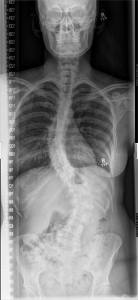

X-ray taken 2009

Scoliosis is a condition where your spine is curved. Some people have one curve, and others, like me, have two curves (Bilateral Scoliosis). Sometimes if you’re diagnosed early in life, meaning before you’re finished growing, it can be reversed or repaired if the curves aren’t too prominent. But for people like me, who didn’t get diagnosed until age twenty two, it is probably too late depending on how advanced the curves are.